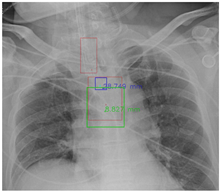

Figure 7 and Figure 8 demonstrate the effect of post-processing. The red bboxes and points in these figures are the GT ETT/bifurcation bboxes and the position of GT ETT tip/Carina, respectively. The green polygon is the GT mask of the ETT and the bifurcation. The blue bbox and point are the predicted ETT bbox and ETT tip, respectively. The yellow bbox and point are the predicted bifurcation and Carina, respectively. Specifically, without the post-process, the model might leave more than one predicted ETT tip/Carina, such as where the red arrow points in Figure 7a. However, with the post-process, the extra points would be removed as shown in Figure 7b. Besides, with the refinement process in the post-process, the feature point of ETT tip/Carina could be further refined as shown in Figure 8. Concretely, the object error of Carina was corrected from 8.469 mm to 1.319 mm.

Figure 7.

Ensuring at most one ETT tip/Carina left. (a) Without post-process. (b) With post-process.

Figure 8.

Refining the feature point of ETT tip/Cairna by the bbox of ETT/Bifurcation. (a) Without post-process. (b) With post-process.